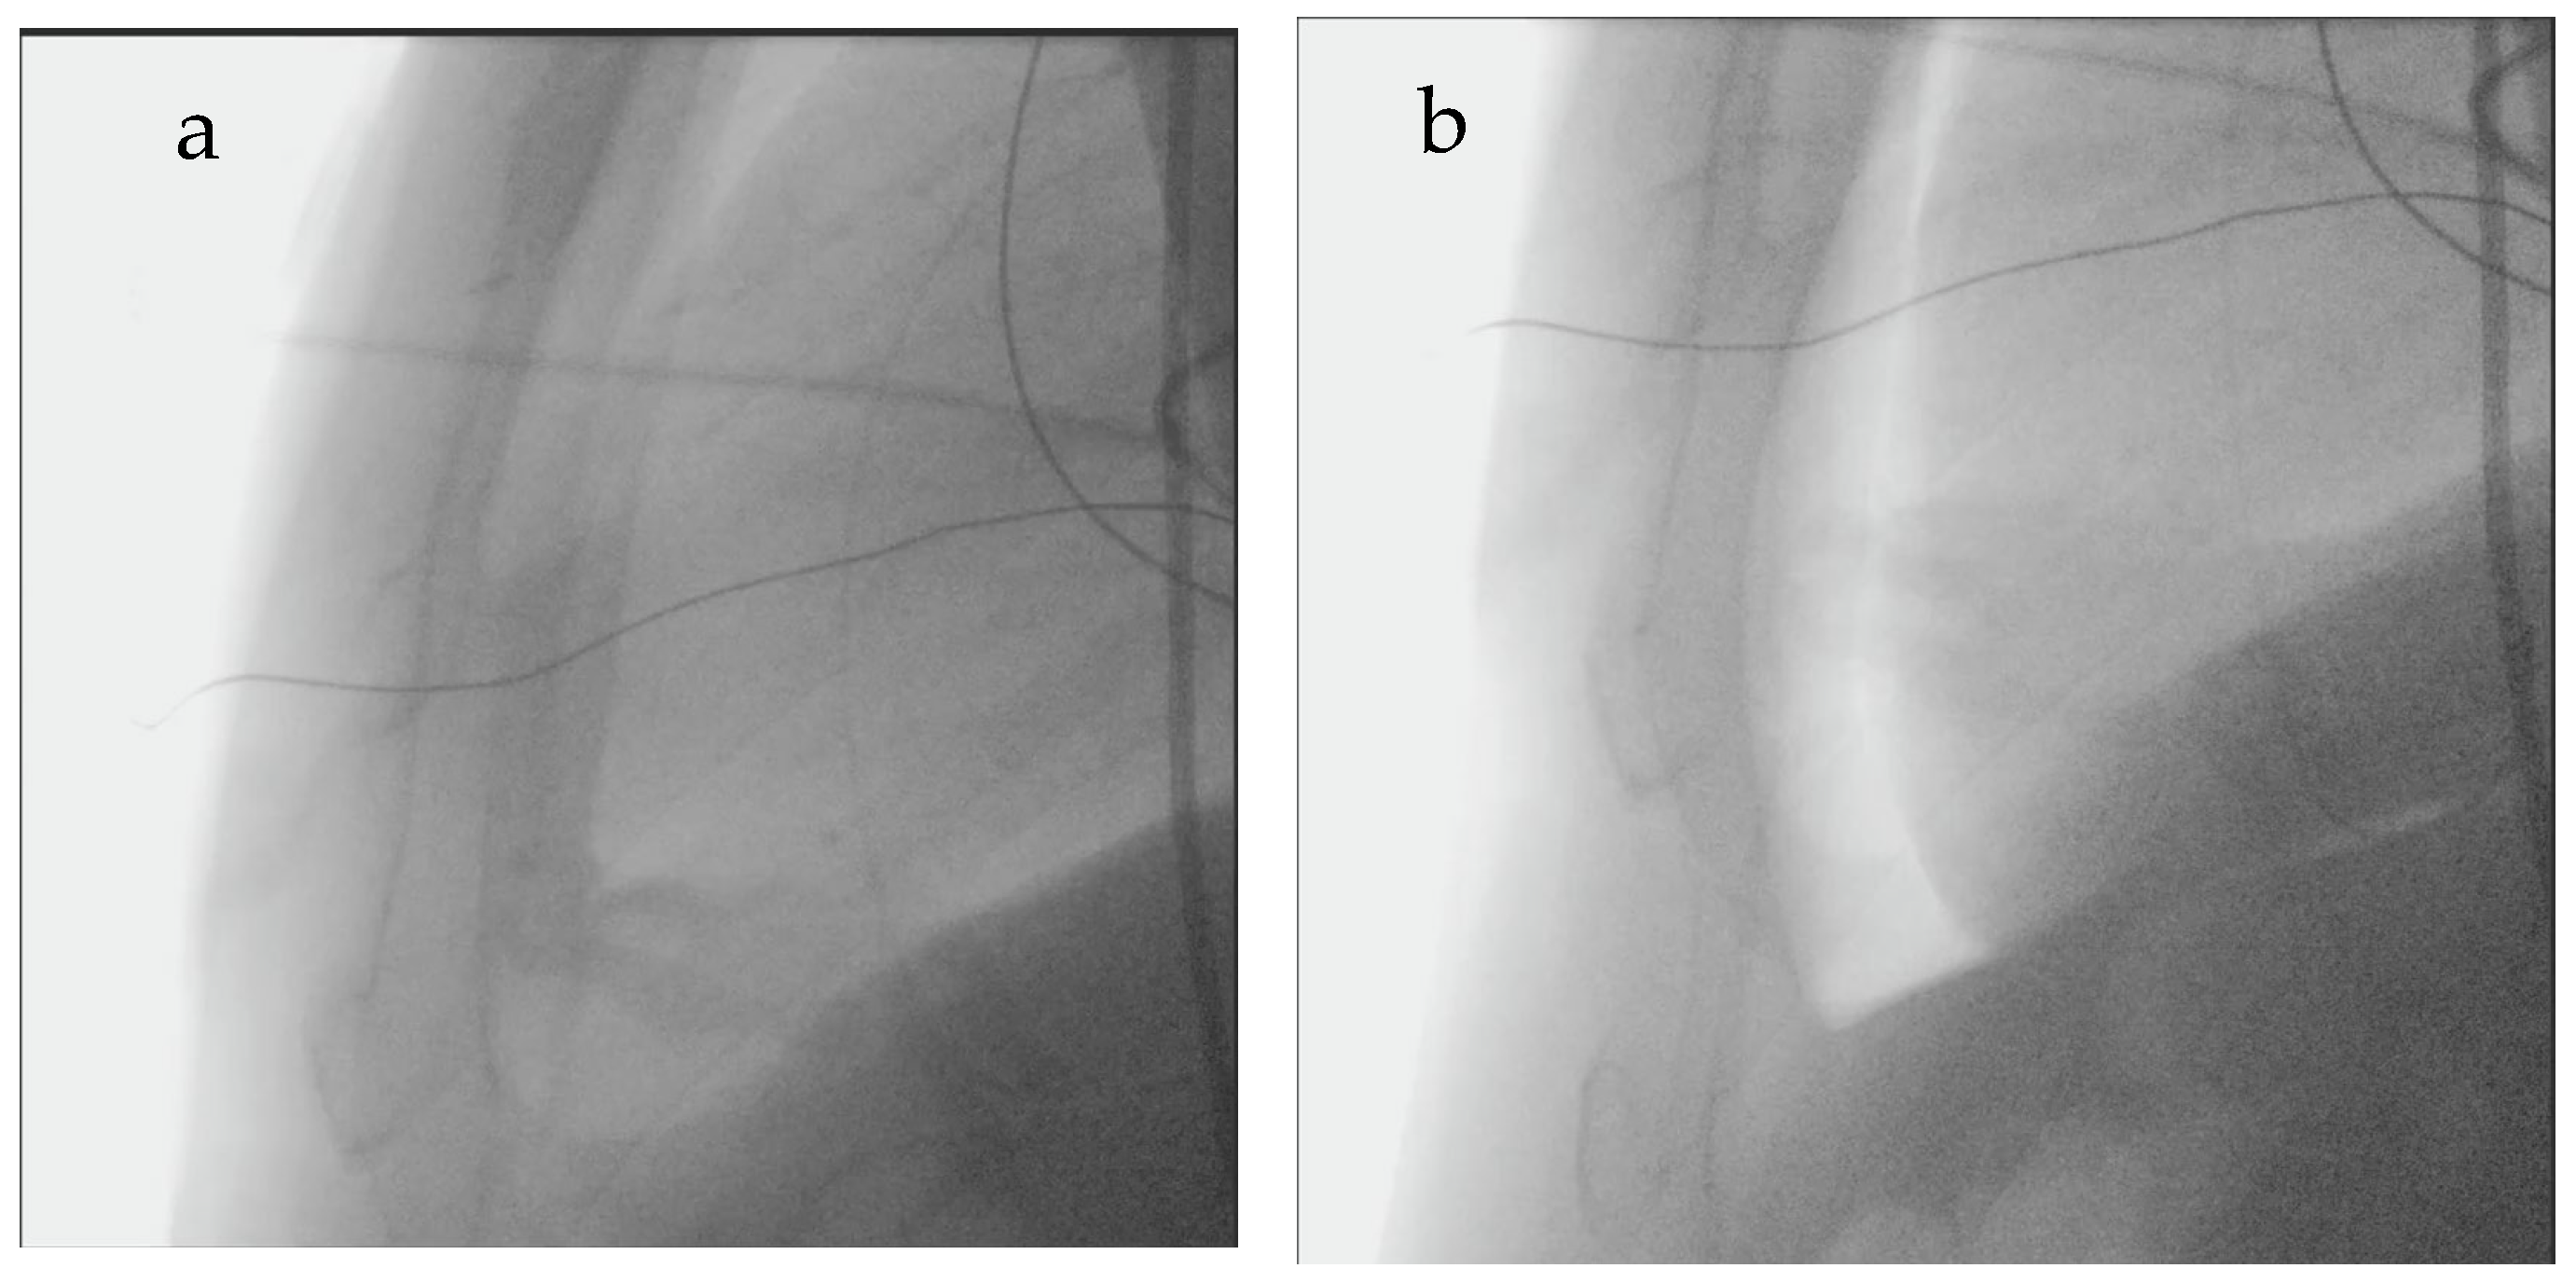

Percutaneous epicardial access through intentional distal coronary vein exit with CO2 insufflation of the pericardial space and subxiphoid microneedle puncture was performed as previously described by Silberbauer et al. [10]. Briefly, using a femoral venous access, an ablation catheter was used to cannulate the coronary sinus (CS) and advance the Agilis introducer. After removal of the ablation catheter, fluoroscopic CS venography was performed, and a branch was then identified and subselected with a JR4 diagnostic coronary catheter and a 0.014-inch angioplasty guidewire. A high-tip-load wire was used to perforate the subselected target vessel, over which an ASAHI Caravel® microcatheter (ASAHI INTECC Co., Ltd., 3-100 Akatsuki-cho, Seto, Aichi 489-0071, Japan) was advanced into the pericardial space. Contrast medium was injected before CO2 insufflation for two purposes: to verify accurate pericardial positioning and to rule out local adhesions that might restrict catheter manipulation, which are known to increase the risk of direct right ventricular perforation. CO2 was insufflated in serial boluses (typically using one or two 50 mL syringes, depending on heart size—larger hearts usually require more CO2 than smaller hearts) until the pericardium and cardiac border could be distinguished or the mean arterial blood pressure decreased by >10 mmHg—Figure 2. Pericardial puncture was then performed using a subxiphoid approach with a Tuohy needle under fluoroscopic guidance. Successful puncture of the pericardium was determined by advancing a guidewire through the needle into the pericardial space with confirmation of appropriate wire position by fluoroscopy and intracardiac echocardiography. A sheath was inserted into the pericardial space to facilitate epicardial drainage, for mapping, and ablation.

Figure 2. Epicardial CO2 insufflation technique. (a) Fluoroscopic image during initial epicardial access, showing minimal separation of the pericardial layers before CO2 insufflation. (b) Fluoroscopic image after controlled CO2 insufflation into the pericardial cavity. The radiolucent CO2 pocket creates a clear separation between the pericardium and the epicardial surface, improving visualization of the pericardial space.